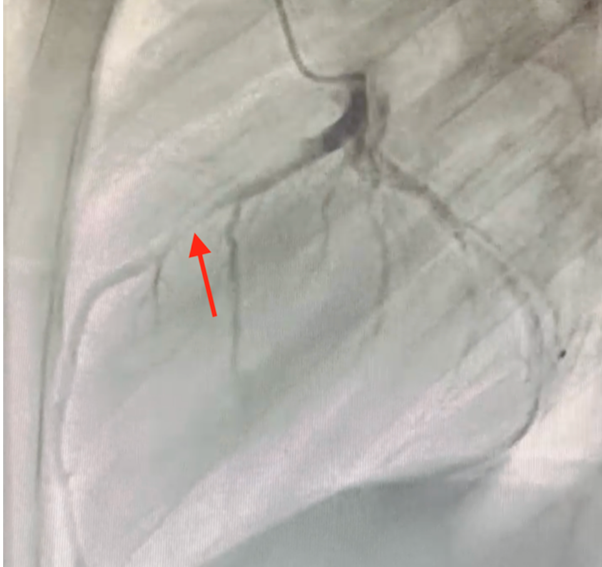

Myocardial bridge involving the LAD is the correct answer choice. This patient's angiograms demonstrated the typical finding of systolic narrowing of the midportion of the LAD (Images 1, 2 [arrows]) but normal appearance in diastole.1

Image 1: RAO 30-Degree Projection

RAO = right anterior oblique.